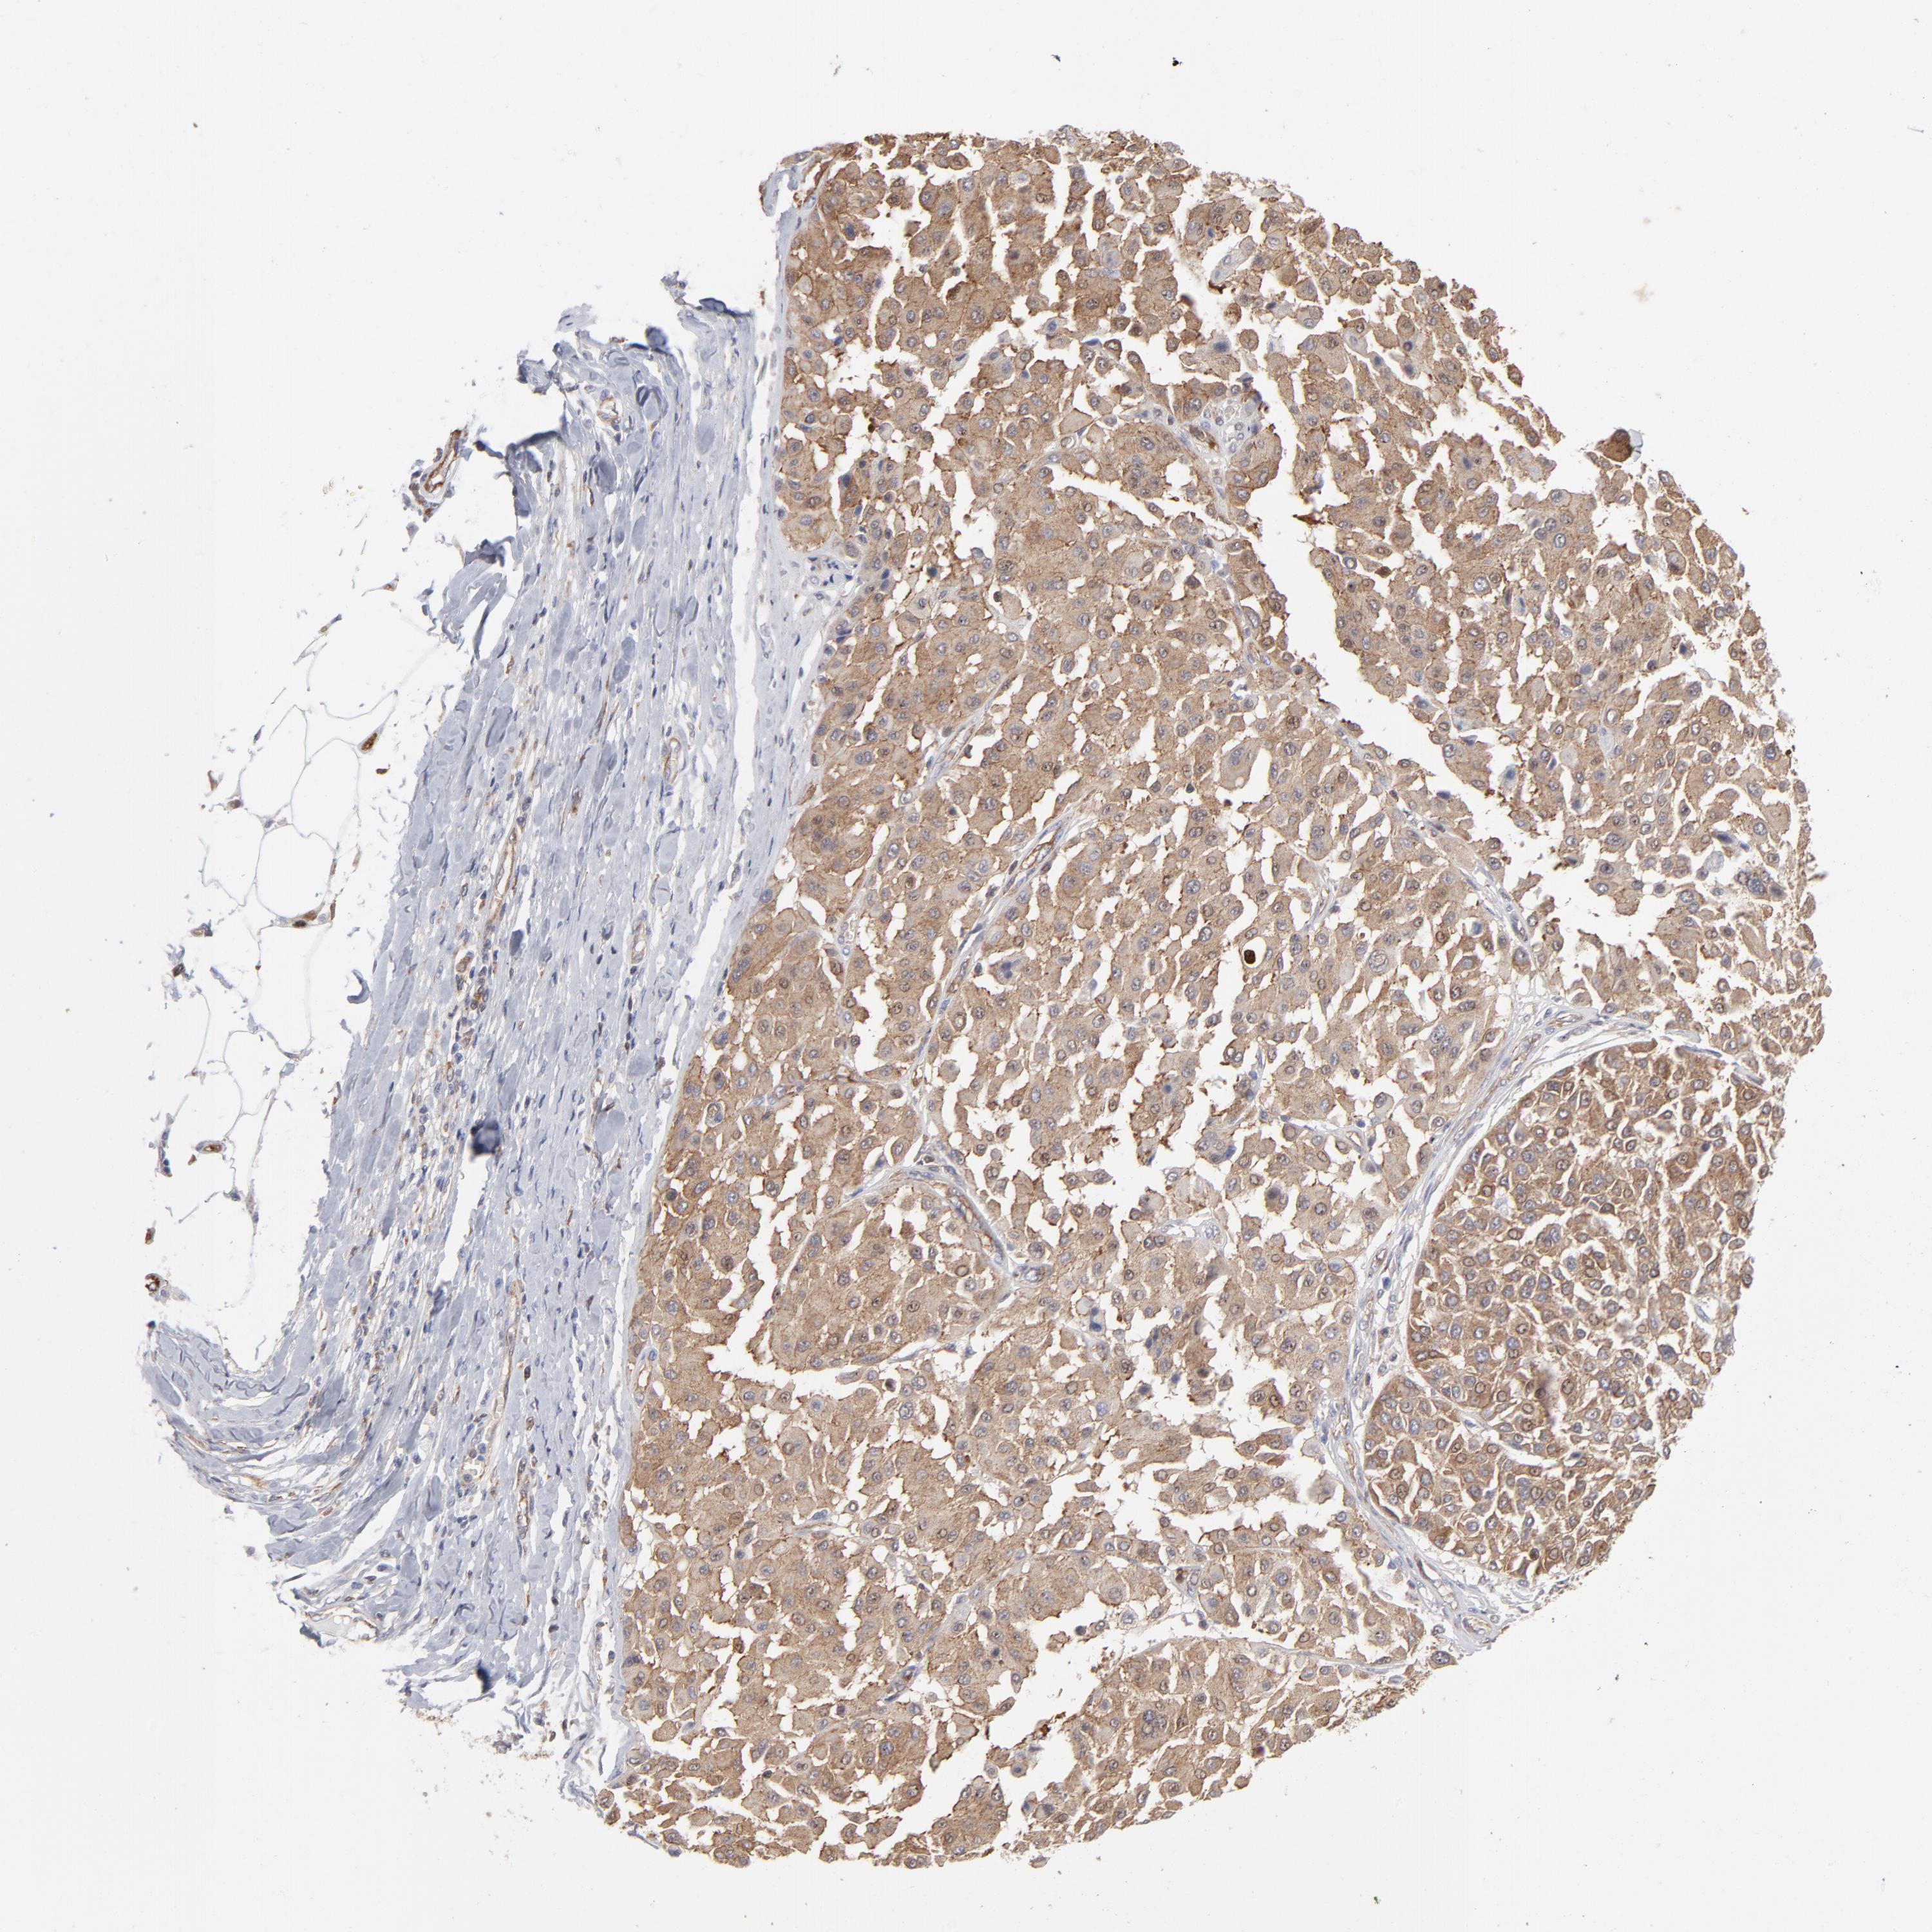

MELANOMA - Protein expressioni

A mouse-over function shows sample information and annotation data. Click on an image to view it in a full screen mode. Samples can be filtered based on level of antibody staining by selecting one or several of the following categories: high, medium, low and not detected. The assay and annotation is described here.

Note that samples used for immunohistochemistry by the Human Protein Atlas do not correspond to samples in the TCGA dataset.

Antibody stainingi

Antibody staining in the annotated cell types in the current human tissue is reported as not detected, low, medium, or high, based on conventional immunohistochemistry profiling in selected tissues. This score is based on the combination of the staining intensity and fraction of stained cells.

Each image is clickable and will lead to virtual microscopy that enables deeper exploration of all samples and also displays staining intensity scores, fraction scores and subcellular localization as well as patient and tissue information for each sample.

Antibody CAB003841

Staining

High

Medium

Low

Not detected

Intensity

Strong

Moderate

Weak

Negative

Quantity

>75%

75%-25%

<25%

None

Location

Nuclear

Cytoplasmic/membranous

Cytoplasmic/membranous,nuclear

Malignant melanoma, NOS

Malignant melanoma, Metastatic site